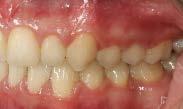

El tratamiento se terminó a los 2 años y 3 meses, en los estudios extraorales finales se ve la coincidencia de la línea media dental superior, con la línea media dental, la exposición dental que muestra la sonrisa (Figura 5), el cambio que se obtuvo en el perfil debido a la retracción del sector anterior.

Se observa el cierre de la mordida, la línea media inferior desviada 1 mm hacia la derecha respecto a la línea

media superior, el overjet de 2 mm y un overbite del 20%, (Figura 6).

Se obtuvo clase I molar bilateral y clase I canina bilateral (Figura 7).